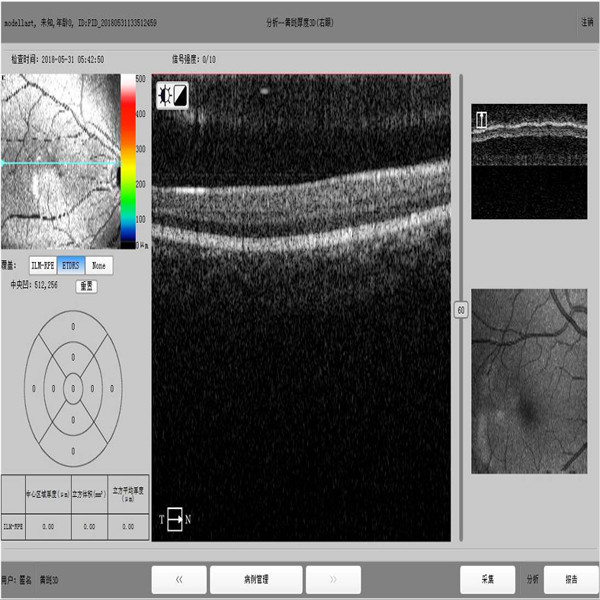

изображение определения офтальмологии машины октября высокие и программное обеспечение всестороннего анализа

Оптически изображения машины томографии сцепления показали что жидкость от ретинальной полости отрыва или расщепления имела каналы водя за зрительным нервом и не имели никакое сообщение с стекловатым телом. Оптически машина томографии сцепления помогает нам к reunderstand природа заболевания, но ОКТЯБРЬ ясно показывает что относящийся к роговице neurocortex утончало и почти исчезало. Если патологическая близорукость не имеет отказ снова весьма мелкого, то выходите из атаки или быть amalamative ретинальным разделением, ретинальное разделение можно увидеть на врожденном и разнообразие заболеваниях как воспаление, травма, denaturation, с больше режимом развертки чем 4 на относящийся к роговице и оптической части, creats программного обеспечения общее annalysis сетчатки пятна, RNFL, ONH. Анализ прогресса для рассмотрения следования доступен.

Спецификации оптически машины томографии сцепления

| Методология | Спектральный домен ОКТЯБРЬ |

| Осевое разрешение | µm ≤6 (в ткани) |

| Поперечное разрешение | µm ≤20 (в ткани) |

| Глубина развертки | ≥2.5 mm (в воздухе) |

| Ряд развертки | ≥6 mm |

| Скорость развертки | ≥24,000 -развертки/sec, до 36 000 -разверток/sec |

| Режимы развертки | 3D, растр, круг |

| Изображение Fundus | Сторона en ОКТЯБРЯ |

| Регулировка фокуса | -15D к +15D |

| Диаметр зрачка | ≥3mm |

| Источник света ОКТЯБРЯ | 840 nm SLD |

| Оптически сила | µW 750 (на роговице) |

| Деятельность | 13,3» экранов касания, опционной внешней мышь или клавиатура |

| Электропитание | 100-240 v, 50/60 Hz |

| Вес размеров | 34 kg (75 lbs) |